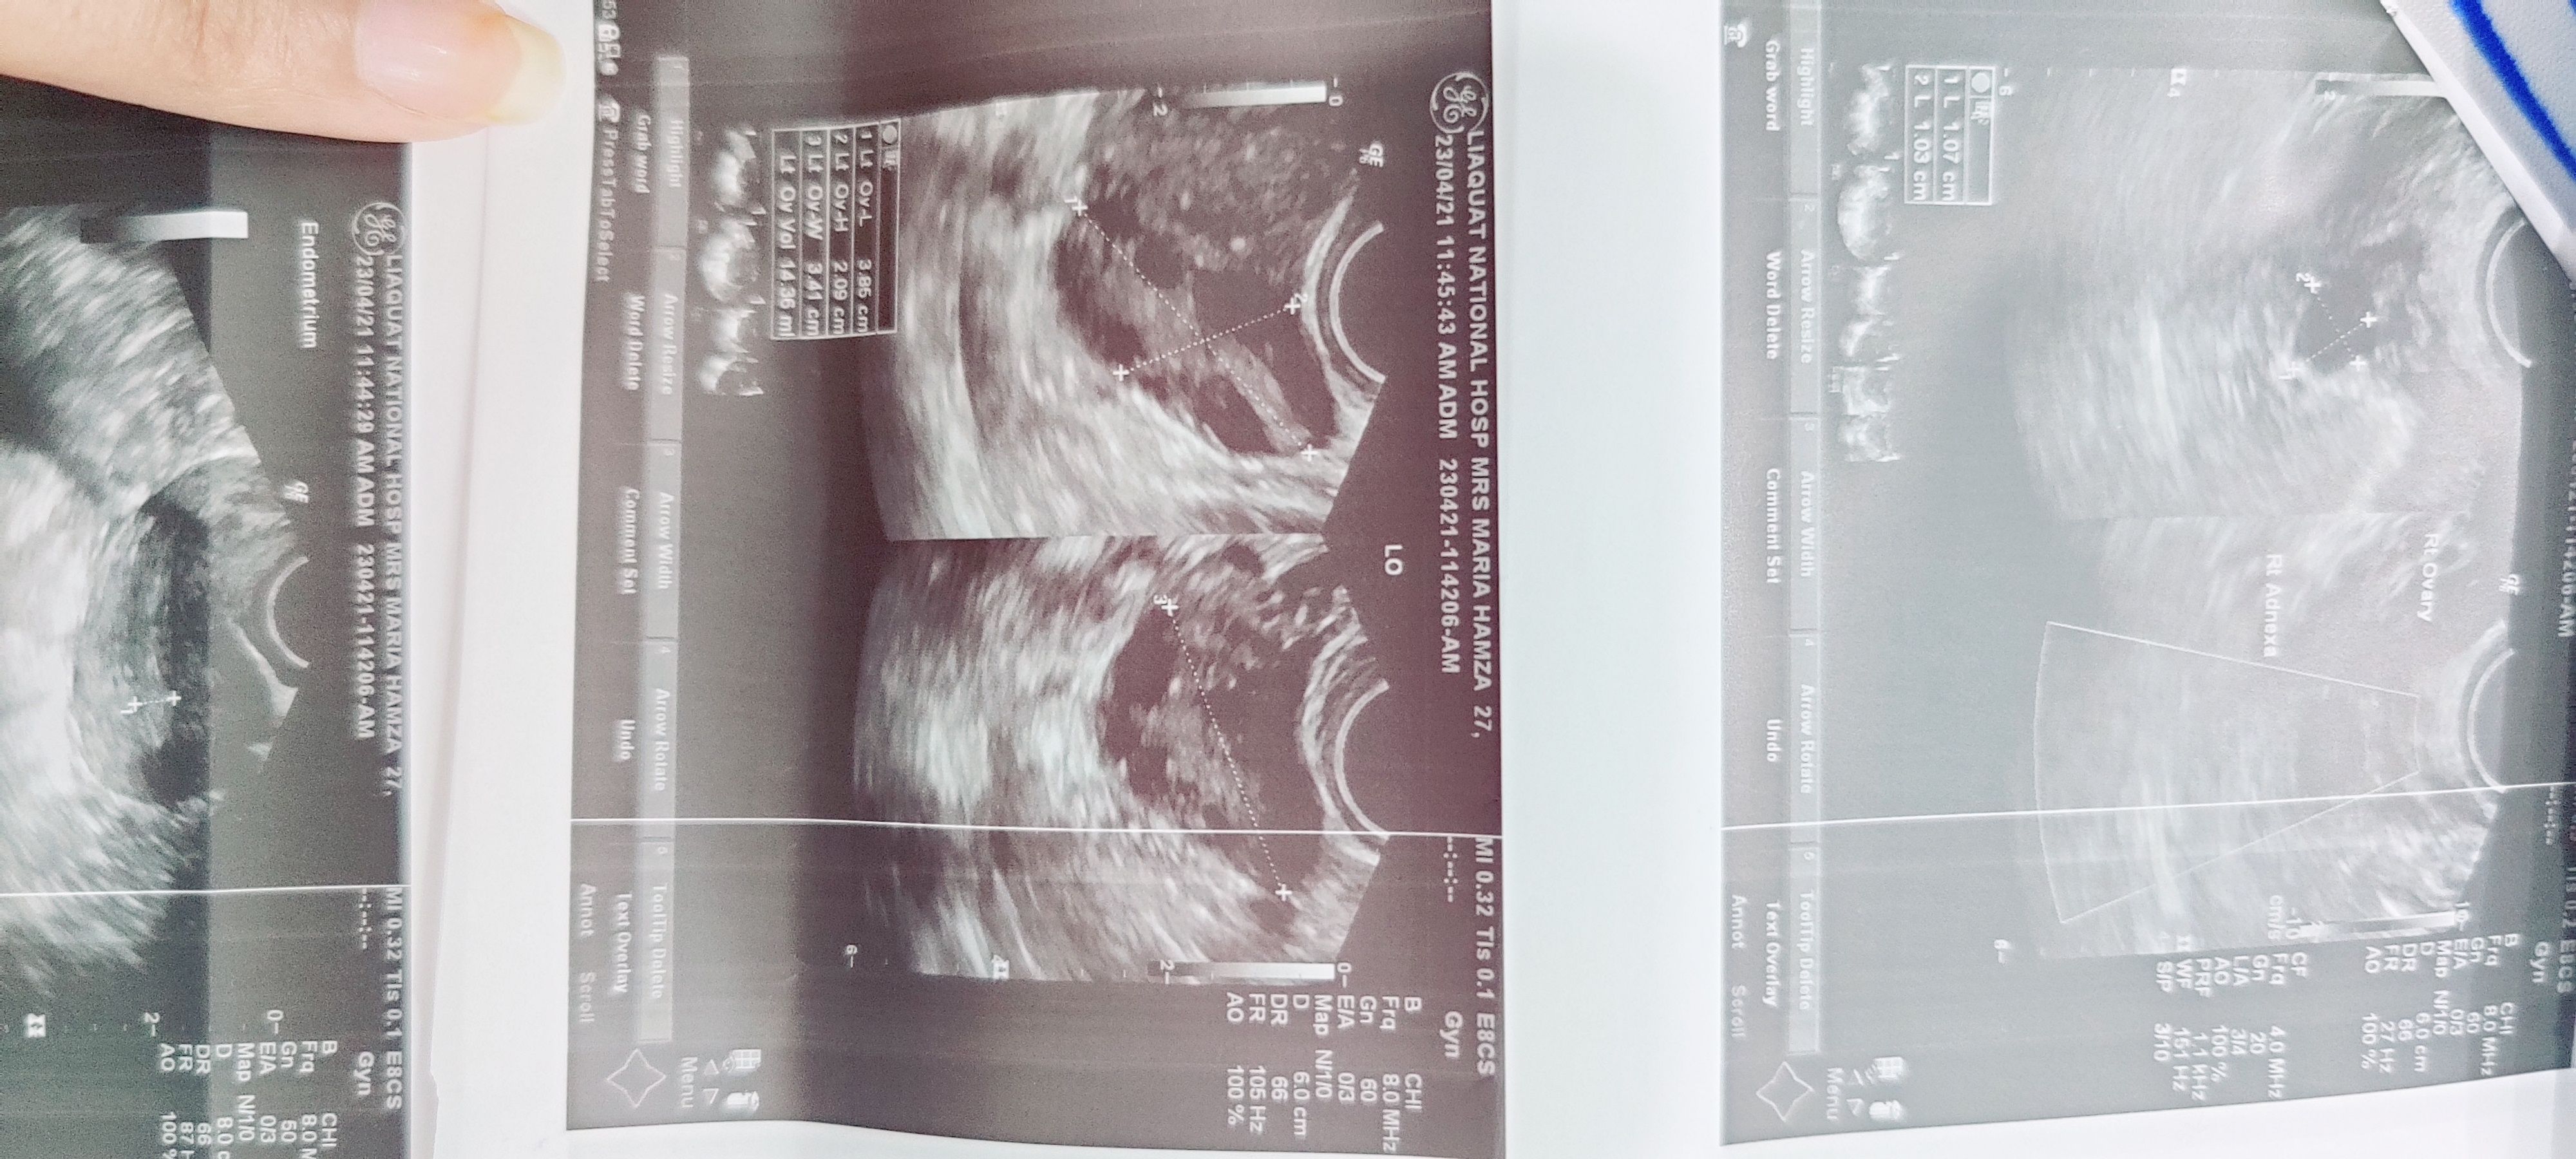

please chk report

ultrasound report after lyposocopy cystonymic

this is my ultrasound report after lyposocopy cystonymic